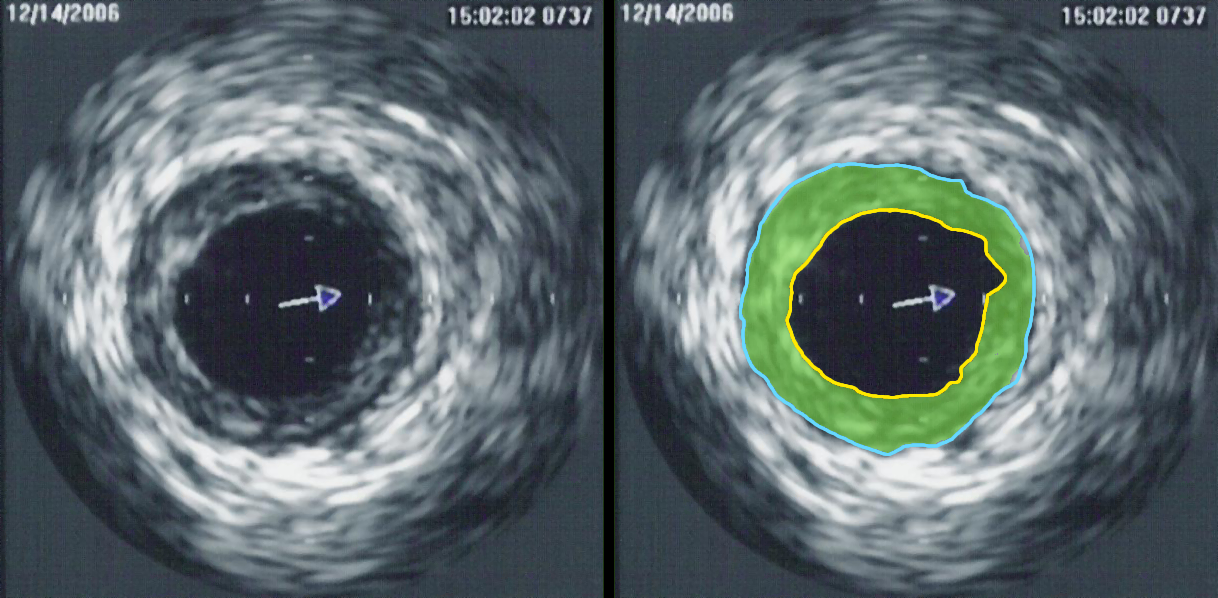

3. 5. 혈관내 초음파 (Intravascular Ultrasound, IVUS)

혈관내 초음파(IVUS)는 카테터를 사용하여 초음파 탐침을 혈관 내부에 삽입하는 특수한 형태의 초음파 검사이다. 이는 혈관의 크기를 측정하고 혈관의 내부 직경을 측정하는 데 일반적으로 사용된다. 예를 들어, 관상 동맥 조영술에서 관상 동맥의 협착을 평가하는 데 사용될 수 있다.[1] 카테터를 조절된 방식으로 뒤로 빼면 혈관과 가지의 윤곽을 볼 수 있는 내부 지도가 생성될 수 있다.[1]